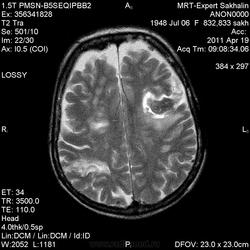

склоняюсь к кровизлиянию в левой теменной долей, начало перехода острой стадии в раннюю подострую( по периферии определяется повышение МРС по Т1 ВИ -метгемоглобин). Справа -старые кортикальные постишемческие глиозно-атрофические изменения. Контрастируется , вероятно за счет формирования участков ангионеогенза.

Это демиелинизирующий процесс, острая стадия, причем с геморрагическим пропитыванием в центре пораженных участков. В принципе, соответствует тяжелому рассеяному склерозу, хотя может быть и геморрагическая форма ОДЭМ. Также могут быть мозговые проявления системного васкулита: надо знать анамнез.

На фоне ДЭП изменений МР-картина ОНМК по ишемическому типу в бассейне ЛСМА с участками геморрагического пропитывания. Аналогичный участок но в более поздней фазе в задних конвнкситальных отделах правой теменной доли.

О.С., я согласен, что контрастирование нехарактерно для ОНМК, ведь в подострую стадию инфаркта наблюдается, как правило, гиральный тип усиления. Плюс, на ОНМК непохоже то, что поражено почти только белое вещество, а кора интактна. И потом, при такой локализации инфаркта обязательно должна быть яркая клиника, и уж никак не только "головная боль".

Что касается снимочков мне кажется что зона патологического сигнала в левой гемисфере можно расценить как подострую стадию ОНМК с геморрагическим пропитыванием, справа как последствия ОНМК. При чем множественные очаги скорей всего как проявление ХМНК. И обязательно рекомендовать контрольное МРТ в динамике . Если это действительно ОНМК на фоне лечения отек уйдет и будет формированиться зона кистозно-глиозных изменений, а если отек будет нарастать значит надо думать о объемном процессе.

ОНМК по геморрагическому типу, почти классика.